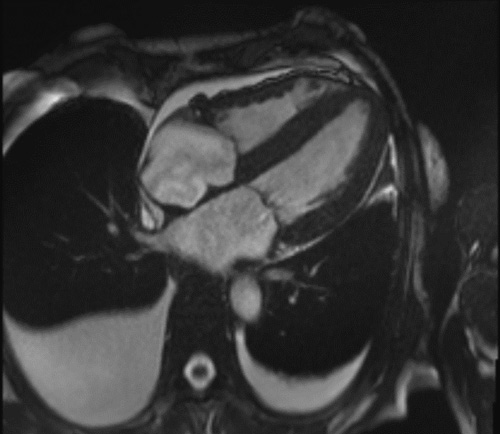

C’est la caractérisation tissulaire qui va permettre de révéler l’infiltration amyloïde caractéristique. Celle-ci va d’abord être suspectée devant un T1 natif myocardique augmenté (valeurs normales entre 950 ms et 1050 ms) en parallèle du volume extracellulaire myocardique (>30%). Cela sera éventuellement ensuite confirmé sur les séquences de rehaussements tardifs après injection de Gadolinium (Figure 6). Les rehaussements tardifs sont généralement très caractéristiques en cas d’amylose cardiaque ; les plus souvent, en « rails » au niveau du septum interventriculaire, ils vont généralement toucher non seulement le ventricule gauche, le ventricule droit mais aussi souvent le septum inter-atrial, les valves et les oreillettes, témoignant d’une atteinte globale du cœur par les dépôts amyloïdes.

Figure 6 : Rehaussements tardifs touchant typiquement les deux ventricules et débutant en sous-endocardiques avec un aspect caractéristique « en rails » du septum inter-ventriculaire en cas d’amylose cardiaque

Assez souvent, on note, lors de la réalisation de l’examen, des difficultés de réglage du temps d’inversion, cela doit d’autant plus faire suspecter le diagnostic d’amylose.

Les rehaussements tardifs en cas d’amylose sont circonférentiels, initialement sous-endocardiques et progressent en transmuralité avec la sévérité de l’infiltration. Le caractère transmural est un facteur pronostic péjoratif. En cas de forte suspicion d’amylose, l’absence de rehaussements ne permet pas d’éliminer complétement le diagnostic et il convient d’avoir recours à des biopsies. Enfin, la scintigraphie « amylose » est parfois plus sensible que l’IRM pour détecter une forme débutante d’amylose TTR.